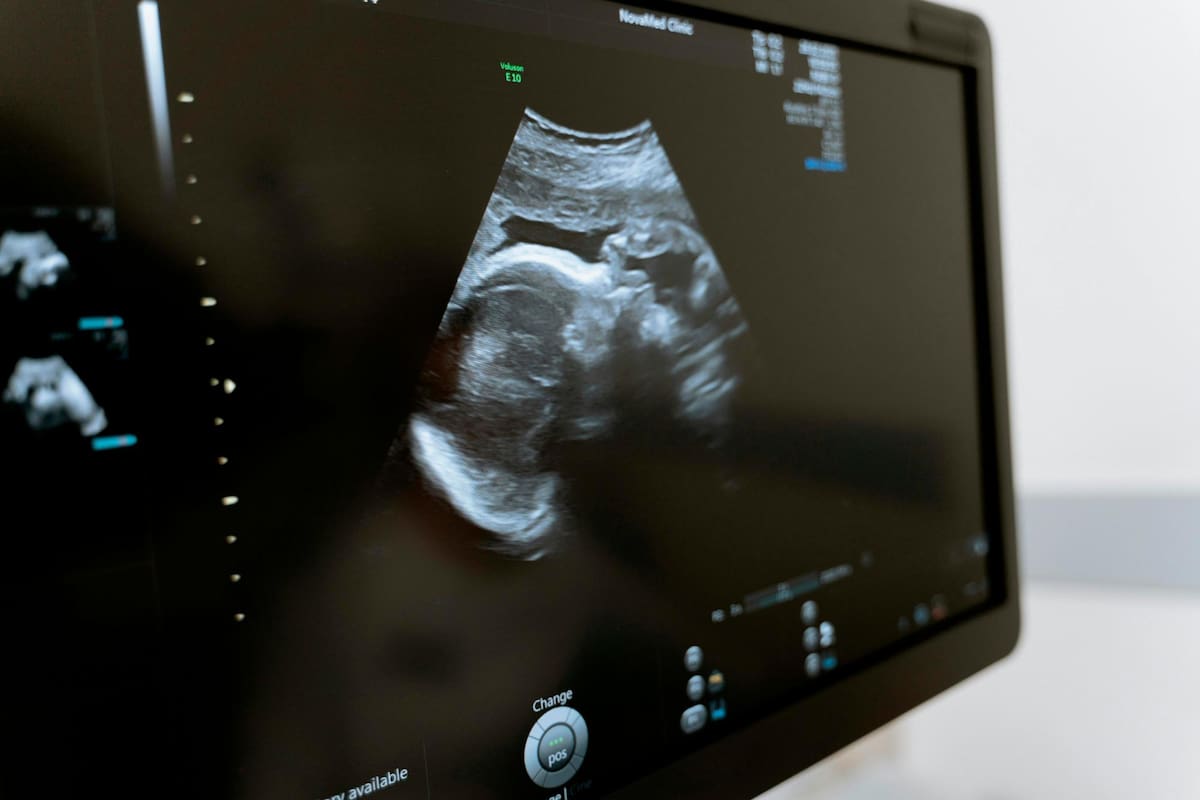

“Es un fenómeno médico poco común en el que un feto muerto se calcifica y permanece en el abdomen de una mujer, generalmente debido a un embarazo ectópico o abdominal”.

Una tomografía computarizada arrojó un sorprendente hallazgo: un “bebé de piedra” dentro del útero de una mujer de 73 años en Argelia

El extraño caso se registró en la ciudad de Skikda, Argelia, donde los doctores quedaron asombrados con las radiografías que le hicieron a la mujer, quien había tenido al ‘bebé de piedra’ por más de tres décadas en su cuerpo.

El bebé de piedra, también descrito como litopedion, se crea cuando se forma un embarazo en el abdomen en lugar de en el útero.

Cuando el embarazo fracasa, el cuerpo no tiene un mecanismo para expulsarlo de forma natural.

En consecuencia, el cuerpo sufre un proceso de calcificación, que esencialmente convierte al feto en una “piedra”, utilizando el proceso inmunológico diseñado para proteger contra cualquier objeto extraño detectado en el sistema de una persona.

Cabe señalar que se trata de una rara condición que, desde su descubrimiento en 1582, solo se han reportado menos de 300 casos de este tipo a nivel mundial.